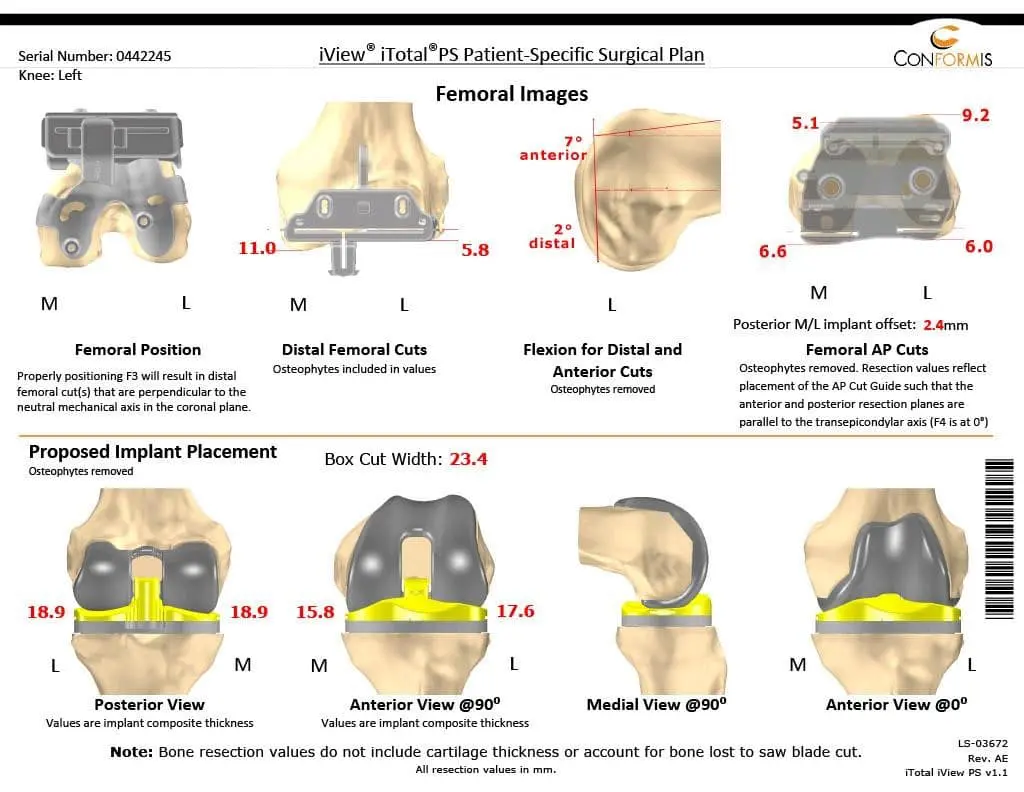

Patient detailed anatomy and biomechanics axis were obtained from a preoperative CT scan. The data obtained was used to construct custom implants. The custom implants were unique for the patient’s anatomy. Disposable 3D constructed jigs were made for accurate bone cuts. A preoperative plan was formed to aid the surgeon in the operation.

Preoperative Surgical plans